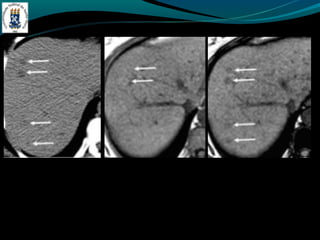

HEMOCROMATOSE

-Primária(hereditária)

-   Aumento da reabsorção gastrointestinal

-   4ª e 5ª década de vida

-   DM, IC, artralgia…

-Secundária(aumento do aporte)

-   Anemia crônica com múltiplas transfusões

-   Ingestão excessiva, porfiria,

-TC: fígado com densidade > 70 HU – sobrecarga de ferro

-Ouro coloidal, doença de Wilson, d. armaz. de glicogênio

-RM: Redução da intensidade do sinal em T1 e T2. hiperintenso

no baço.

-Hemossiderose, d. de Wilson…

HEMOCROMATOSE -Primária(hereditária) - Aumento da reabsorção gastrointestinal - 4ª e 5ª década de vida - DM, IC, artralgia… -Secundária(aumento do aporte) - Anemia crônica com múltiplas transfusões - Ingestão excessiva, porfiria, -TC: fígado com densidade > 70 HU – sobrecarga de ferro -Ouro coloidal, doença de Wilson, d. armaz. de glicogênio -RM: Redução da intensidade do sinal em T1 e T2. hiperintenso no baço. -Hemossiderose, d. de Wilson…